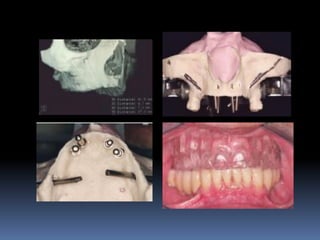

Exames Imaginológicos

Radiografias periapicais, telerradiografias e

panorâmicas;

Tomografias computadorizadas

Softwares de imagens 3D

Modelos de estudo

Enceramento diagnóstico

Guia cirúrgica

Visão espacial do planejamento a

executar